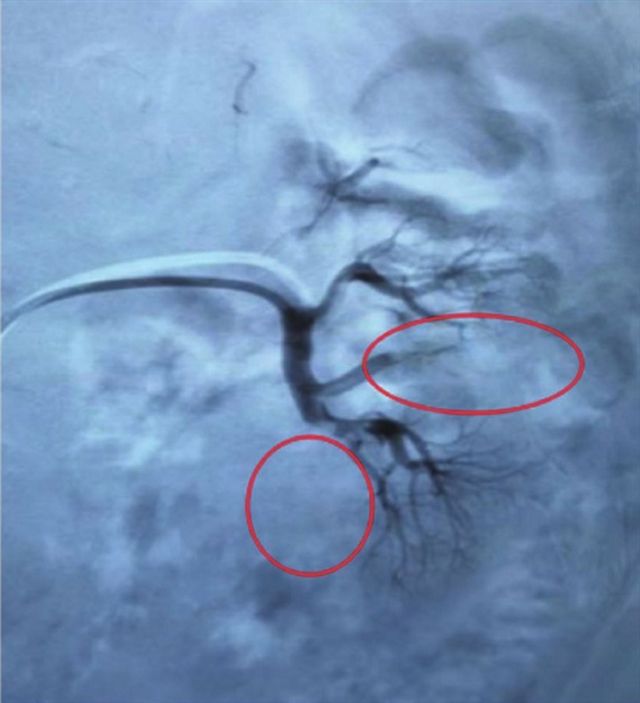

治疗前可见肾动脉支下极肾动脉(2支)充盈缺损,远端肾皮质显彰欠佳,梗死面积约50%~70%

心脏瓣膜病变+急性肾梗死等多器官栓塞,刘先生命悬一线,需要紧急救治。“肾梗死治疗的关键是尽早恢复肾脏血流,其标准化治疗包括抗凝及溶栓治疗”,鉴于此,张克勤教授团队立即给与低分子肝素钠抗凝治疗,同时请心血管内科、血管外科、神经内科等相关科室紧急联合会诊,结合刘先生左肾大面积梗塞的状况,确定了采取溶栓治疗方案,以尽可能恢复患者肾功能。

当晚,为刘先生行经右侧股动脉穿刺左肾动脉造影+置管溶栓术,因为经介入手术精准插入导管,使堵塞血管部位顺利溶栓。术后,张克勤教授团队再次与血管外科共同制订患者治疗方案,给与精准用药。